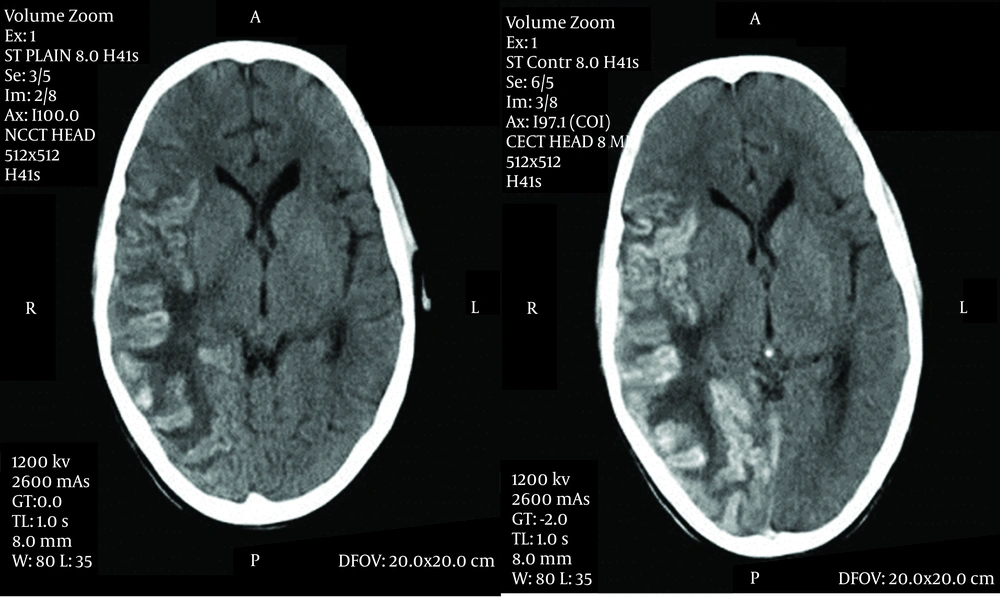

Tuberculosis is known to cause wide variety of systemic complications when it disseminates in the body. Tuberculosis, suppressing all three cell lines which causes pancytopenia, leading to aplastic anemia has been reported by very few case reports, either as the result of disseminated tuberculosis or as an adverse effect of anti-tubercular medicines (1-3). An eleven-year-old male, weighing 27 kg with poor nutritional status presented to our pediatric intensive care unit with history of fever for one month, headache and vomiting for 15 days and weakness of right half of his body with right-sided deviation of the angle of his mouth for 3 days. He also noticed bluish spots on the chest and trunk for one day. He lived in an overcrowded house with illiterate parents and belonged to a family with low socioeconomic status, but was immunized and had BCG scar with a history of contact with an active tuberculosis patient in his family. He did not have similar complaints in the past or any hospitalization or medication. On examination, the child was afebrile and normotensive, his heart rate was 110 beats per minute, and respiratory rate was 27/min. He was severely pale, and petechiae were observed over the trunk accompanied by subconjunctival hemorrhage. He was drowsy with altered sensorium. Neurological examination revealed meningoencephelitis with right sided hemiparesis with left sided facial palsy. The examination of other systems was within normal limits. Cerebrospinal fluid analysis revealed 432 mg/dL protein, 43 mg/dL glucose, 110 meq/L chloride with 160 cells out of which 75% was lymphocytes and 25% was polymorphs. Gram staining of the CSF was unremarkable and culture was negative. However, CSF PCR was positive for mycobacteria tuberculosis. There were few signs of raised intracranial pressure without active seizure. He was given supportive treatment with intravenous fluids, mannitol, and dexamethasone. When he was stabilized on the second day, antitubercular therapy and nasogastric tube feeding were initiated. Brain CT showed gyral swelling with patchy hemorrhage involving fronto-parieto-temporo-occipital lobe (meningo-encephelitis) with grade 3 perifocal edema leading to mild leftward midline shift (Figure. 1).